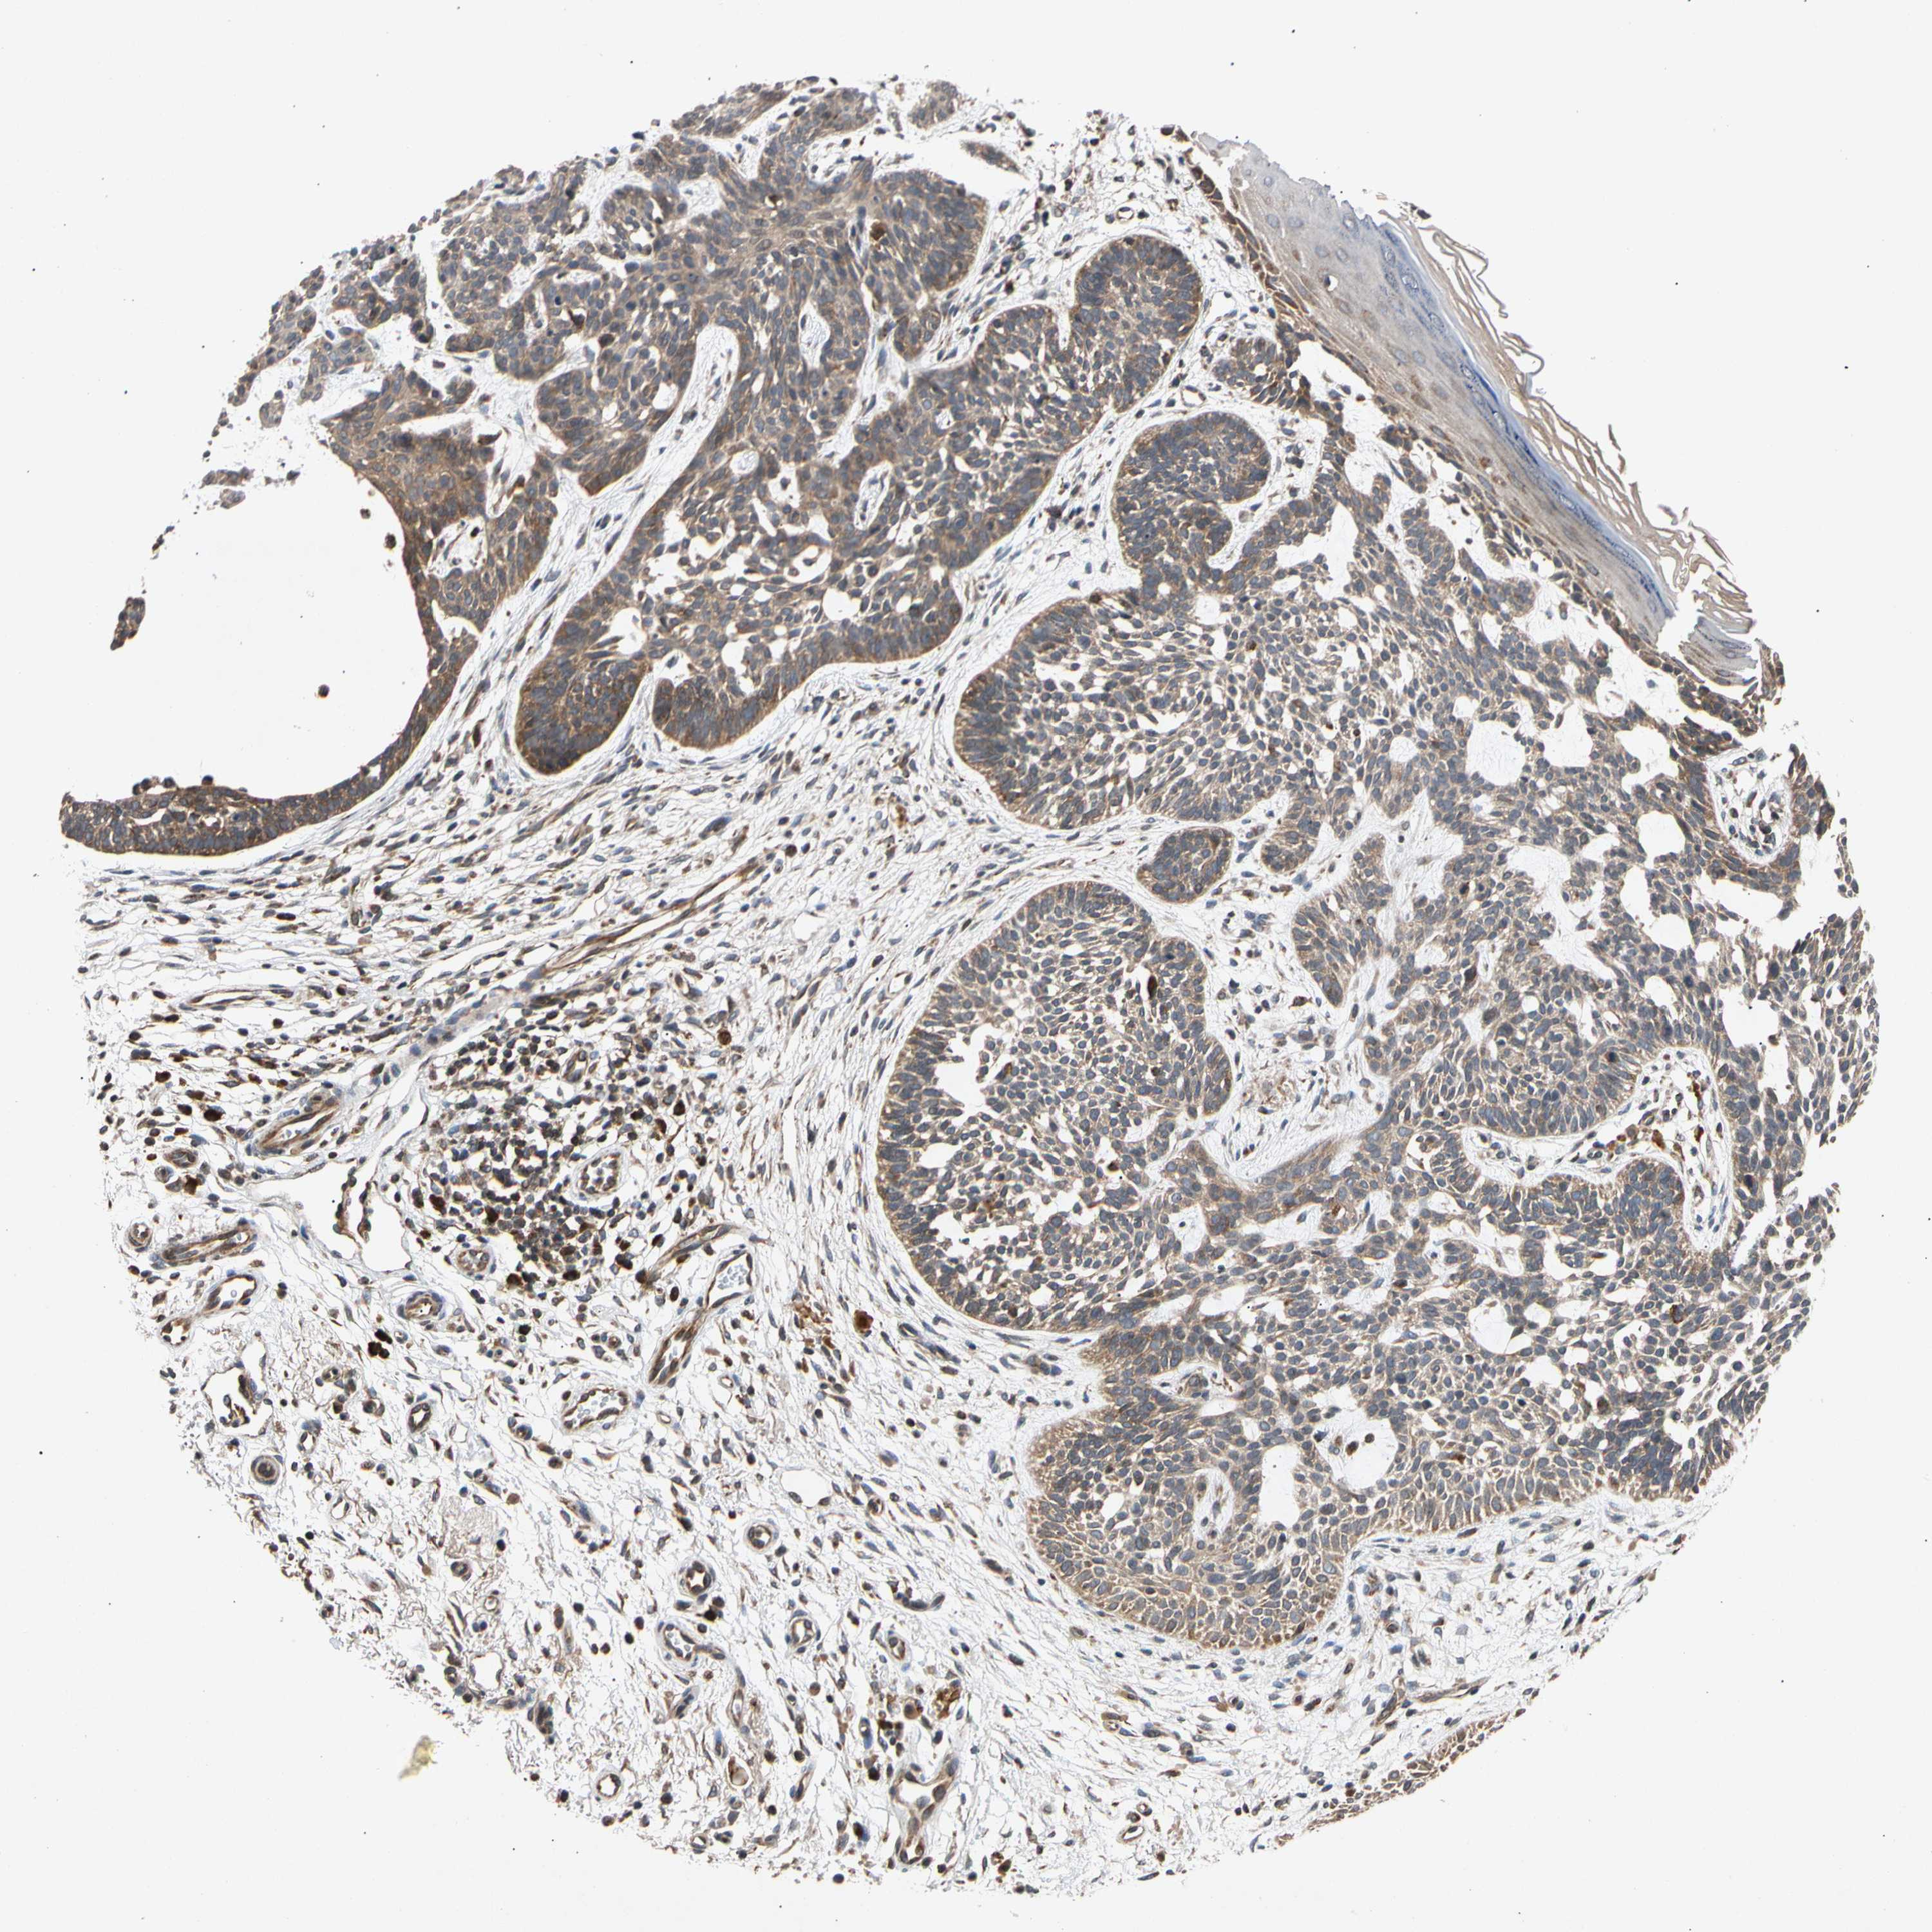

Basal cell and squamous cell cancer

SKIN CANCER - Protein expressioni

A mouse-over function shows sample information and annotation data. Click on an image to view it in a full screen mode. Samples can be filtered based on level of antibody staining by selecting one or several of the following categories: high, medium, low and not detected. The assay and annotation is described here.

Antibody stainingi

Antibody staining in the annotated cell types in the current human tissue is reported as not detected, low, medium, or high, based on conventional immunohistochemistry profiling in selected tissues. This score is based on the combination of the staining intensity and fraction of stained cells.

Each image is clickable and will lead to virtual microscopy that enables deeper exploration of all samples and also displays staining intensity scores, fraction scores and subcellular localization as well as patient and tissue information for each sample.

Antibody HPA007830

Squamous cell carcinoma, NOS

Basal cell carcinoma